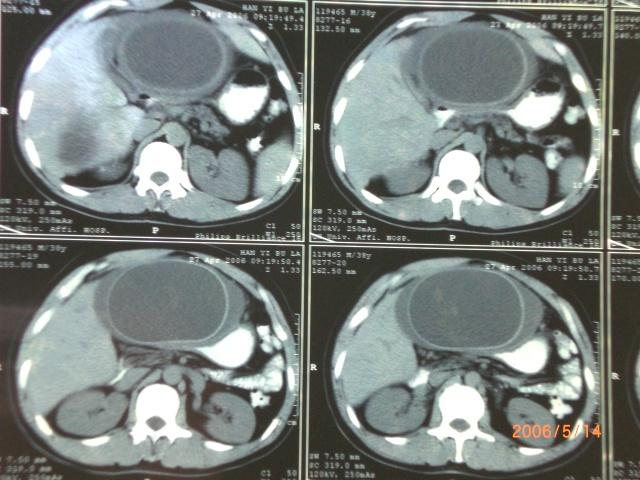

肝包虫ct增强图片

【读片】包虫病典型ct,有兴趣的请踊跃发言 [病例帖]

【病例学习】肝包虫病一例ct诊断